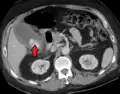

| Acute cholecystitis as seen on CT. Note the fat stranding around the enlarged gallbladder. | |

Acute cholecystitis with gallbladder wall thickening, a large gallstone, and a large gallbladder -